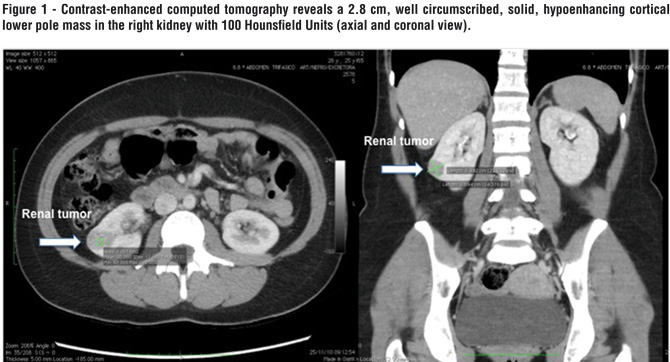

Laboratory screening included serum sodium, calcium, potassium, aldosterone, renin, cortisol, catecholamines, and urinary metanephrines. Initial work-up revealed mild hypokalemia (3.4 mEq/L) and increased renin levels (7.7 ng/mL/h) with normal aldosterone (22 ng/dL). Other hormone levels were within normality. Doppler ultrasound did not reveal any abnormality in renal vessels flow. However, a 2.5 cm hypoecogenic mass was found in the right kidney. Contrast-enhanced computed tomography of the abdomen demonstrated a 2.8 cm, well circumscribed, solid, hypoenhancing cortical lower pole lesion in the right kidney with 100 Hounsfield Units (Figure-1). The patient was counseled on options regarding radical nephrectomy and nephron-sparing surgery, as well as alternative for open or laparoscopic intervention. She decided for laparoscopic partial nephrectomy and the procedure was accomplished without intra-operative complications. Total surgical time was 120 minutes and renal hilum clamping time was 14 minutes. Bleeding was negligible. The patient had an uneventful recovery and was discharge home in postoperative day one. Histopathologic examination revealed a rare juxtaglomerular cell tumor known as reninoma (Figure-2) after minucious immunohistochemical analysis, which was negative for Cytokeratin 35BH11, EMA, CD 34, CD 56, S-100, Chromogranin A, HMB-45, WT-1, and CD 31; and positive for AML (areas), vimentin (focally), ACTIN HHF35 (rare cels), and CD 117 (focally). Patient’s blood pressure normalized within 2 months of surgery (Systemic Blood Pressure < 120x90 mmHg), allowing withdrawn of all medications.